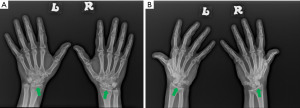

Due to the high suspicion of ILD, the primary care physician requested a high-resolution computed tomography (HRCT) scan, which showed fine reticular opacities in the posterior regions of both lower lobes of her lungs and a ground-glass nodule (GGN) in the apical segment of the right upper lobe, with some subpleural sparing, as illustrated in Figure 2. The patient was subsequently referred to a respiratory physician, who diagnosed early ILD associated with OS. She was managed with regular follow-ups to monitor disease progression using lung function tests and HRCT. The prognosis of the condition and the potential need for immunosuppressive therapy in the future were discussed with the patient.

Given the strong suspicion of ILD, the primary care physician ordered an HRCT scan of the chest to confirm the diagnosis and evaluate its severity. HRCT is regarded as the gold standard to detect ILD because of its high sensitivity (18). In this case, the scan results revealed bilateral reticular opacities and GGN, indicating early changes of ILD, prompting referral to a respiratory physician for further evaluation. It can be argued that ILD is a well-recognized manifestation of SSc and not necessarily a complication or related to OS. However, in this case, ILD was manifested in the presence of both SSc and RA, supporting the diagnosis of OS.